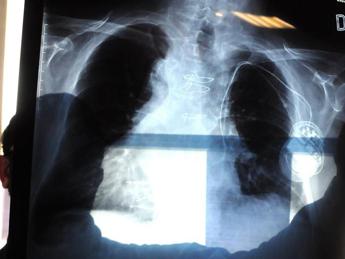

(Adnkronos) – "In Italia l'amianto è presente ancora ovunque e anche in modo insospettabile, senza che nessuno intervenga". Lo denuncia Antonio Giordano, oncologo italiano in forze negli Usa, dove è arrivata forte la testimonianza del giornalista Franco Di Mare che ha rivelato la malattia contratta presumibilmente negli anni trascorsi da inviato di guerra nei Balcani. La sua storia "ha scosso anche l'America. Siamo al suo fianco", dichiara all'Adnkronos Salute lo scienziato, presidente della Sbarro Health Research Organization (Shro) e professione alla Temple University di Philadelphia. Da un lato "urge eliminare definitivamente l'amianto presente nell'ambiente", dall'altro "serve mettere a punto un adeguato sistema di monitoraggio degli ex esposti", esorta Giordano, convinto che invece "interessi economici rallentano la ricerca scientifica". "Il mesotelioma pleurico – spiega l'oncologo – è un killer silente, ma allo stesso tempo è uno dei pochi tumori per cui l'eziologia è pressoché certa: lo sviluppo di questa neoplasia è certamente correlato all'esposizione a fibre di amianto". Giordano lo sa bene, sia perché "studio il mesotelioma da tantissimi anni" sia perché "posso definirmi un 'figlio d'arte'. Mio padre Giovan Giacomo Giordano – racconta – fu uno fra i primi scienziati, insieme al professor Cesare Maltoni del Collegium Ramazzini di Bologna, a studiare e a scoprire i gravissimi danni derivati dall'esposizione alle fibre di amianto e anche grazie alle sue ricerche l'amianto è stato messo fuori legge in Italia nel 1992". Un bando adottato "a livello europeo dal 1999". Eppure di mesotelioma si continua a morire e accade "per due motivi", ragiona lo scienziato. Innanzitutto per la "lunga latenza clinica del tumore, considerando che tra l'esposizione al minerale e lo sviluppo della malattia possono intercorrere fino a 30 anni". E poi perché, "nonostante ogni attività di estrazione, commercio, importazione, esportazione e produzione di amianto, prodotti di amianto o prodotti contenenti amianto sia stata vietata, il materiale è ancora presente in grandi quantità – avverte Giordano – nei luoghi in cui non si è provveduto alla bonifica e allo smaltimento". "L'aria avvelenata, anche dall'amianto, continua a far male" tanto che "ormai il rischio di sviluppare mesotelioma è diventato ambientale – precisa l'oncologo – piuttosto che professionale. Le peculiari caratteristiche fisico-chimiche dell'amianto giustificano il suo vastissimo utilizzo nell'edilizia per cui, se è presente in grandi quantità in zone come l'Italia, si può solo immaginare quante fibre di residui tossici ci possano essere in zone coinvolte da azioni belliche: residui derivanti dalla distruzione di edifici, dalla combustione e dall'ossidazione di inquinanti che restano in sospensione nell'aria, che penetrano nelle falde acquifere e nei terreni coltivati. Scenari che hanno visto coinvolto il giornalista Franco Di Mare". Giordano ha all'attivo diversi lavori focalizzati sul mesotelioma pleurico, "poiché nonostante gli enormi progressi in ambito scientifico – puntualizza – questa neoplasia ancora oggi è orfana di marker diagnostici, prognostici e soprattutto di approcci terapeutici efficaci". Lo scienziato, campano 'doc' nato a Napoli, ha vissuto in prima linea anche la battaglia dei lavoratori dell'ex Isochimica di Avellino: "Una vera bomba ecologica", dice. "Il quartiere di Borgo Ferrovia, nel centro città – ricorda – ha respirato per anni un'aria intossicata dall'amianto. Lo certificano le perizie disposte dalla procura, a cui ho partecipato". "Ad oggi non vi è alcun test che da solo o in combinazione con altri possa essere utilizzato per campagne di prevenzione che possano essere avviate a livello di popolazione", fa notare l'oncologo. Bisognerebbe quindi affinare le armi diagnostiche per poter avviare un monitoraggio sugli ex esposti alle fibre d'amianto. "Invece oggi si assiste a un rallentamento degli studi", che per Giordano "potrebbe essere causato dai forti interessi economici alla base dell'industria dell'amianto". A maggior ragione, dunque, "nelle aree ad alto rischio di patologie asbesto-correlate – insiste lo scienziato – è indispensabile intervenire bonificando nel più breve tempo possibile. Non si può temporeggiare per motivi economici e condannare a morte migliaia di persone". —[email protected] (Web Info)